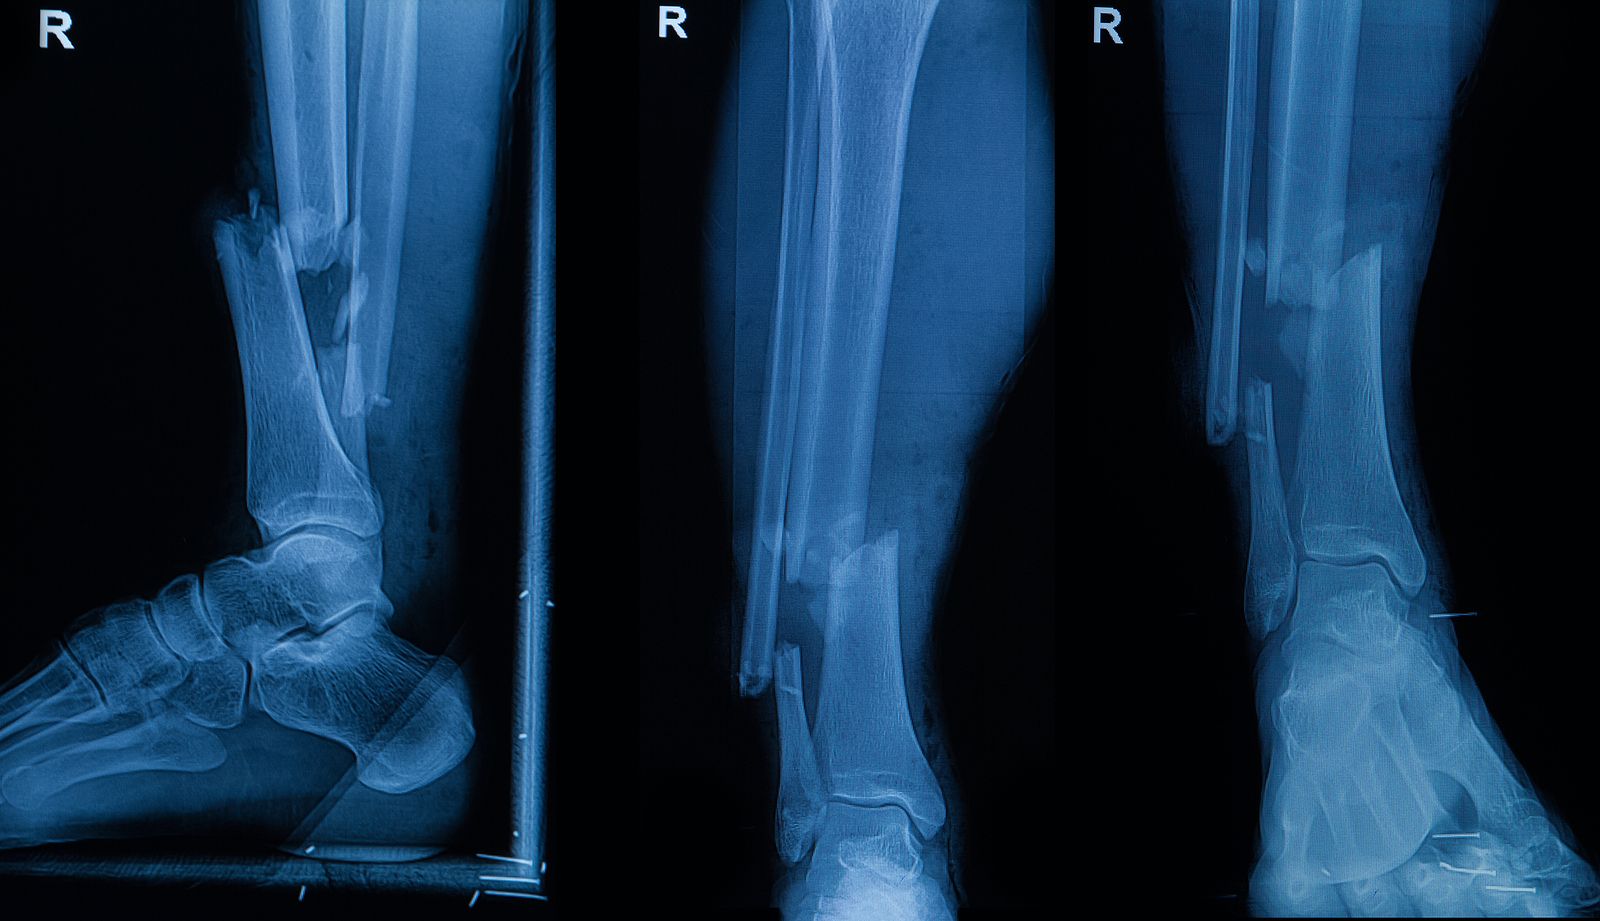

Las fracturas, una de las lesiones clínicas más comunes, son una causa importante de discapacidad en pacientes jóvenes y de mediana edad, así como de mortalidad en pacientes mayores. Con los avances en la tecnología médica moderna, en particular el uso de dispositivos metálicos de fijación interna, como tornillos y placas, el pronóstico general de las fracturas ha experimentado una transformación drástica. Sin embargo, las fracturas conminutas, que involucran numerosos fragmentos óseos pequeños, aún representan un gran desafío clínico.

Fracturas de pequeños fragmentos

Los métodos tradicionales de fijación metálica tienen dificultades para lograr una reducción anatómica. Fijar pequeños fragmentos óseos requiere mucho tiempo y esfuerzo, y a menudo no logra una alineación precisa y uniforme. Durante el proceso, pueden perderse o reabsorberse fragmentos óseos, lo que provoca una pérdida irreversible de masa ósea, un retraso en la consolidación o incluso la falta de unión.

Este problema es especialmente grave en las fracturas conminutas, donde una reducción imprecisa puede provocar fácilmente defectos o irregularidades en la superficie articular, que eventualmente progresan a artritis traumática y afectan gravemente la calidad de vida de los pacientes. Encontrar tratamientos más eficaces y mínimamente invasivos para estos casos sigue siendo uno de los mayores desafíos en ortopedia.